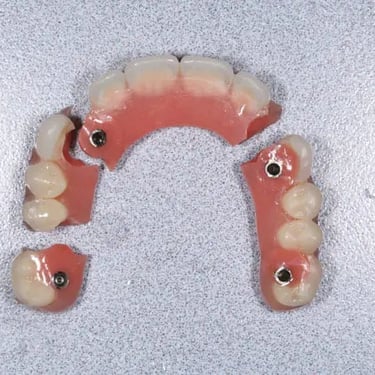

Edentulismo completo

El edentulismo completo es la ausencia total de dientes en una o ambas arcadas.

Los pacientes tienen dificultad para masticar, hablar y pueden sentirse incómodos con su apariencia.

El tratamiento puede incluir la colocación de una prótesis completa sobre implantes, proporcionando una solución fija y estable